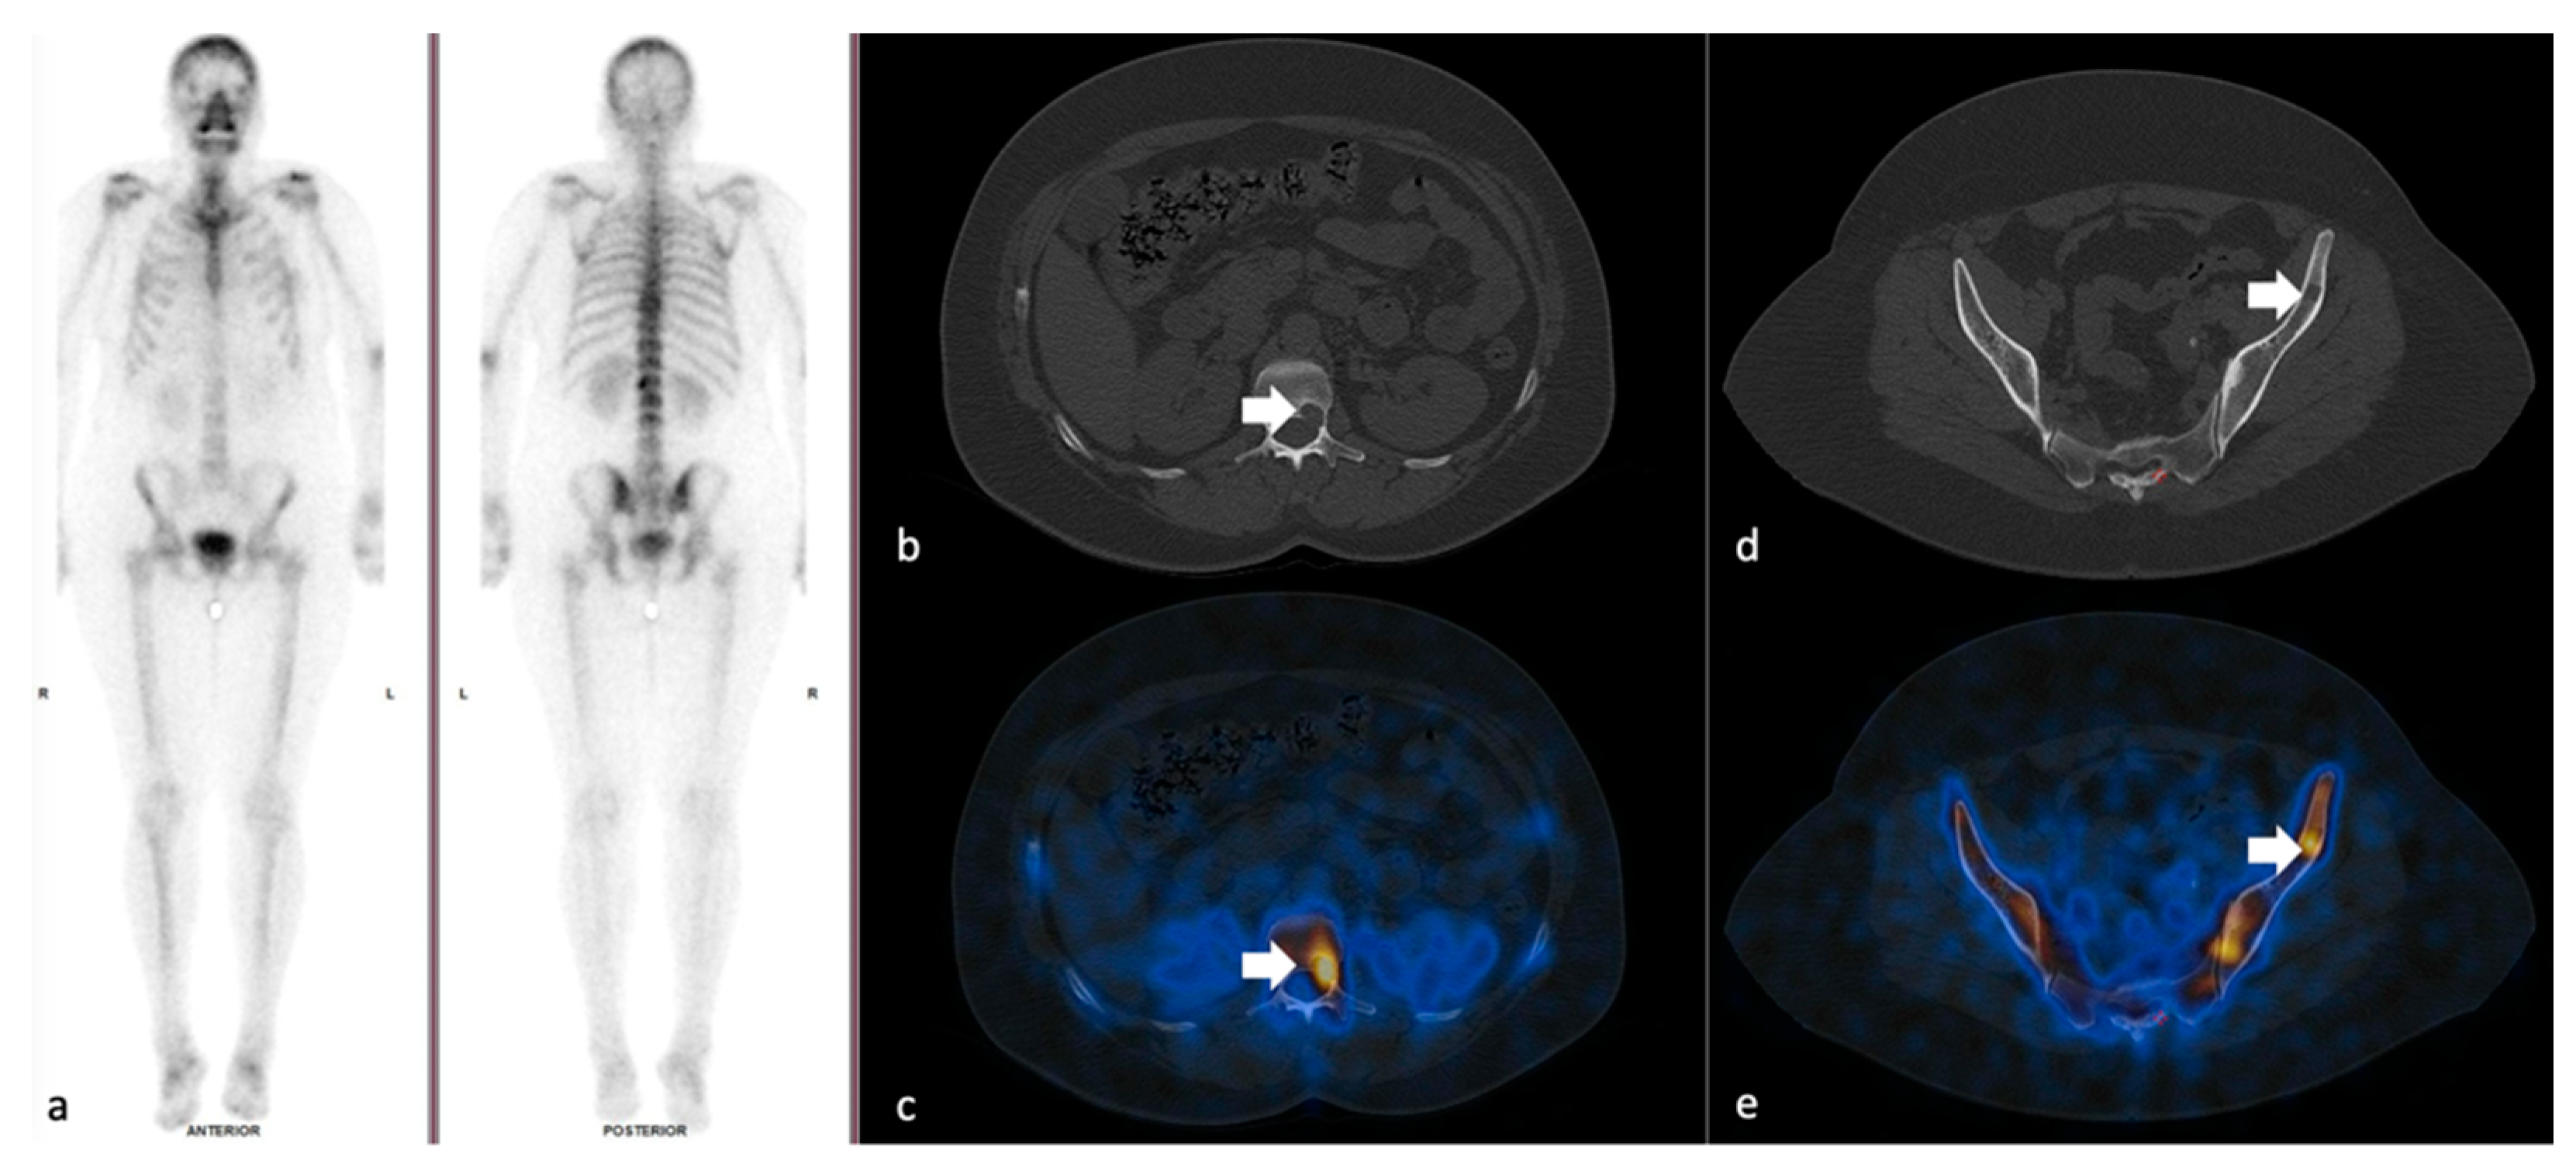

3.2. SPECT-CT SUVmax in Metastatic Lesions and Degenerative Bone Disease

3.3. SUVmax Cutt-off Value in Differentiating between Degenerative and Metastatic Lesions